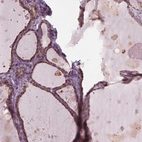

Immunohistochemistry analysis in human thyroid gland and skeletal muscle tissues using Anti-DNASE2 antibody. Corresponding DNASE2 RNA-seq data are presented for the same tissues.